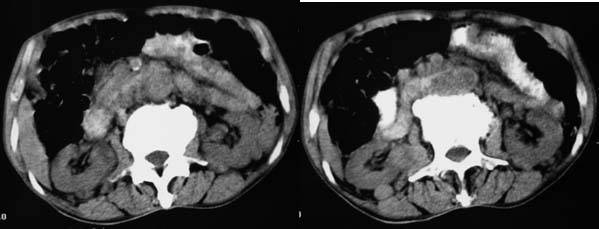

上腹部横断图象显示:心包,胃体小弯侧,肾等器官周围以及肠系膜腹膜后多发的大小不等的小结节样软组织密度影,部分境界不清,未见明显钙化.如此广泛的小结节样影,我认为首先考虑淋巴结肿大.能够引起淋巴结肿大的最常见的原因为:1.炎症(结核常见);2.转移;3.淋巴瘤.其中淋巴结结核不同程度可见钙化,而且这么大范围少见,暂不考虑.

右侧肾上腺区可见软组织密度肿块,密度欠均匀,未见钙化;右肾下极内侧可见实质局限性增厚并呈肿块样突出肾轮廓.

肝胃间隙,双侧肾周间隙,腹主动脉旁类圆形软组织结节影,首先考虑是增大的淋巴结。

从平扫看:左肾上腺区域见软组织结节,内见钙化。

右侧肾上腺区软组织肿块影,密度不均,其周围及腹主动脉周围,心包周围均见多个淋巴结肿大.结合临床首先考虑:右肾上腺恶性肿瘤伴腹腔内及心包淋巴结转移.